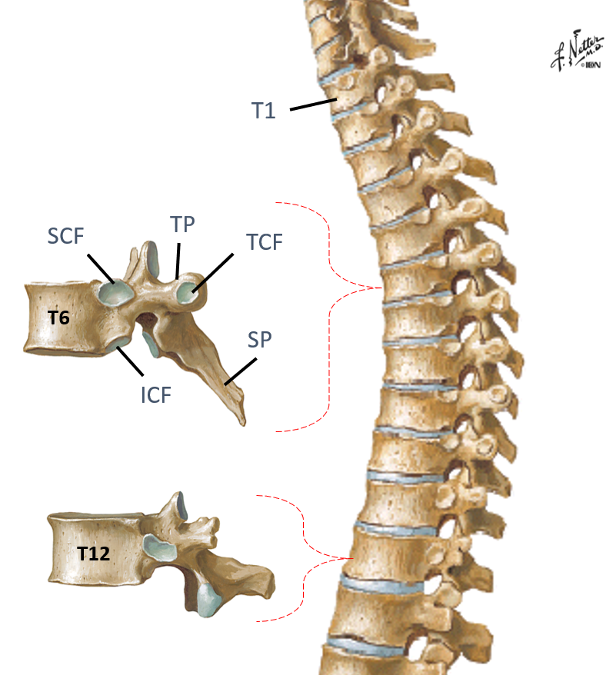

Identify the landmarks thoracic vertebrae 1-12

Spinous process

(SP)?

Transverse process (TP)?

Costal facets along vertebral

bodies (CF)?

Transverse costal facets (TCF)?

study picture

look at picture

what do the costal facets have along the vertebral bodies, except for where?

what is the transverse costal facets along? except for where?

Costal facets along vertebral bodies (CF)...Pairs of inferior (ICF) and superior (SCF) on vertebrae except lower 4 thoracic vertebrae

Transverse costal facets (TCF)..along transverse processes except lower 2 thoracic vertebrae...notice how T12 in pic does have a transverse costal facet

in theory, typical ribs should articulate with what?

2 vertebrae